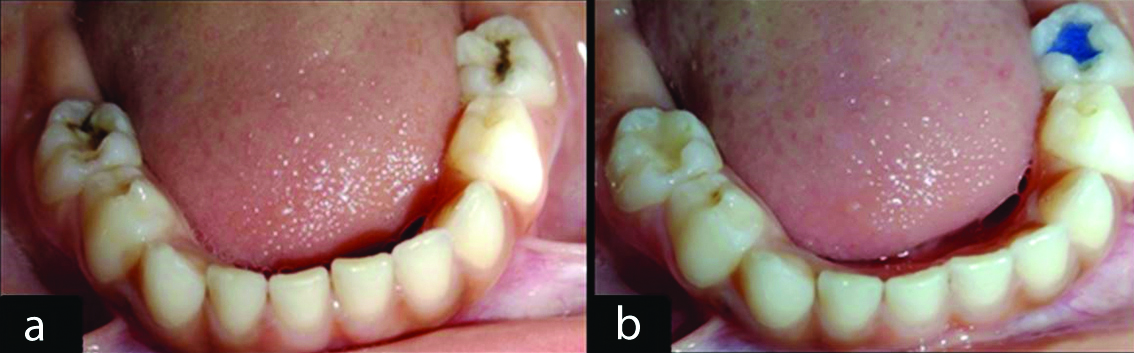

During the restorative procedure, the armamentarium used is shown in [Table/Fig-2a,b]. Isolation was initially achieved using a rubber dam to ensure optimal working conditions. The carious lesion was then removed using a rotary high-speed handpiece, followed by careful cavity preparation. Etching was performed using 37% phosphoric acid for 15 seconds, after which the cavity was thoroughly rinsed and dried. Subsequently, a bonding agent was applied and cured for 15 seconds [Table/Fig-3a,b]. Composite material was then placed incrementally, with each layer being light-cured for 20 seconds. Articulating paper was utilised to verify occlusal irregularities.

Armamentarium. a) Bilateral occlusal caries with 75,85. b) 75 with bule coloured composite, 85 with tooth coloured composite.